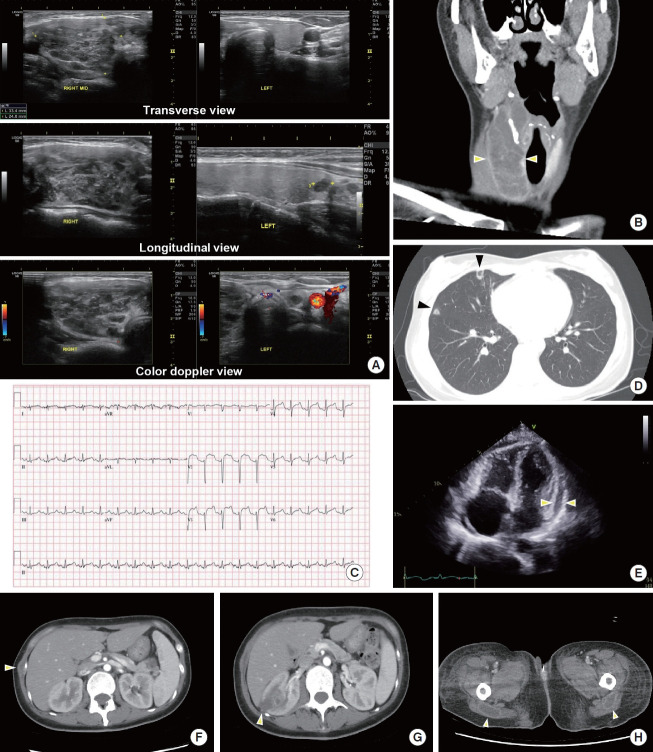

Abstract Image